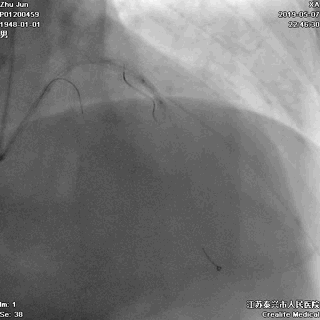

二、导丝到位

---筑牢生命线

导丝分别进回旋支和前降支

LAD和LCX,任一根血管都不能丢!这一步的价值,就相当于是构筑生命线。